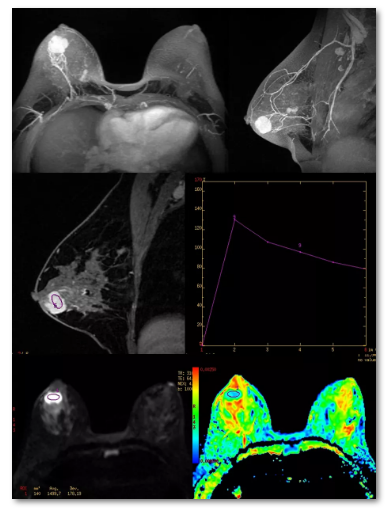

具有良好的软组织分辨率和无射线辐射特点,对乳腺检查具有独到的优势。

乳腺MRI检查具有以下优势:

·软组织分辨率高,对发现乳腺病变具有较高的敏感性,特别适于观察致密型乳腺内的肿瘤;

·MRI三维成像使病灶定位更准确、显示更直观;

·多参数成像,不仅可以显示病变的形态学信息,还可以提供病灶血流动力学、水分子扩散及肿瘤代谢等功能学信息,有助于良、恶性病变的鉴别及疗效评估;

·对多中心、多灶性病变的检出较为敏感,对胸壁侵犯的观察以及对腋窝、内乳区的显示较为敏感,可为乳腺癌的准确分期和临床制订治疗方案提供可靠的依据;

·对以腋窝淋巴结转移为首诊的隐匿性乳腺癌患者,有助于发现乳腺内原发灶;

·可准确观察乳房假体位置,确认有无破裂等并发症;

·无射线辐射性。